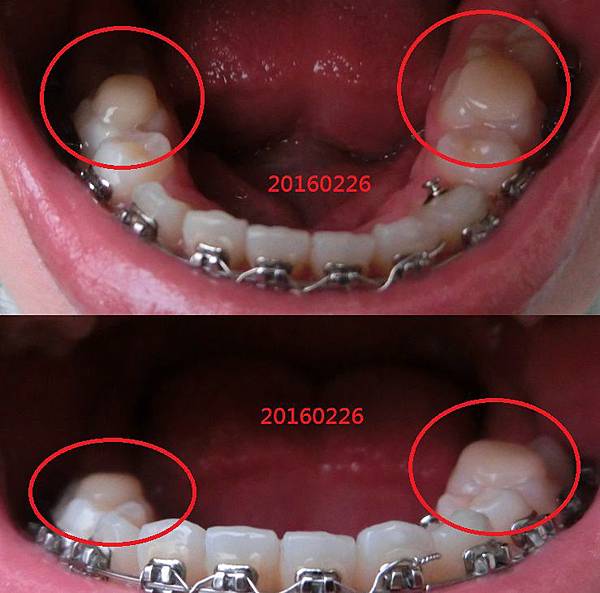

- 2月 10 週三 201621:25

﹝牙套日記﹞ 牙套905天 骨釘掰掰 大暴牙掰掰